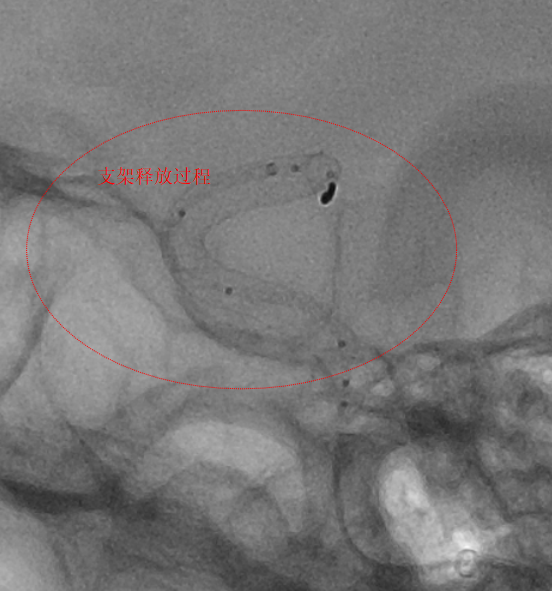

第二例患者为左侧大脑中动脉动脉瘤,该部位血管解剖结构复杂,对手术的精准度要求极高。团队使用血流导向装置,支架完美打开及贴壁,患者术后3天顺利出院。